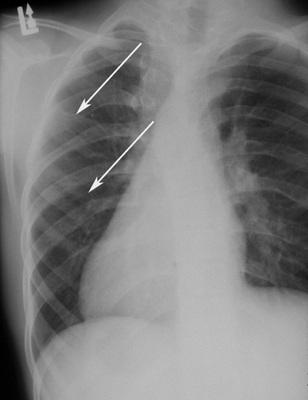

Radiographic Features

- multiple odontogenic keratocysts (90%)

- frontal and temporal bossing

- calcified falx cerebri

- splayed, bifid, or fused ribs

nevoid basal cell carcinoma syndrome (Gorlin syndrome)

Chest film showing presence of bifid ribs.

nevoid basal cell carcinoma syndrome